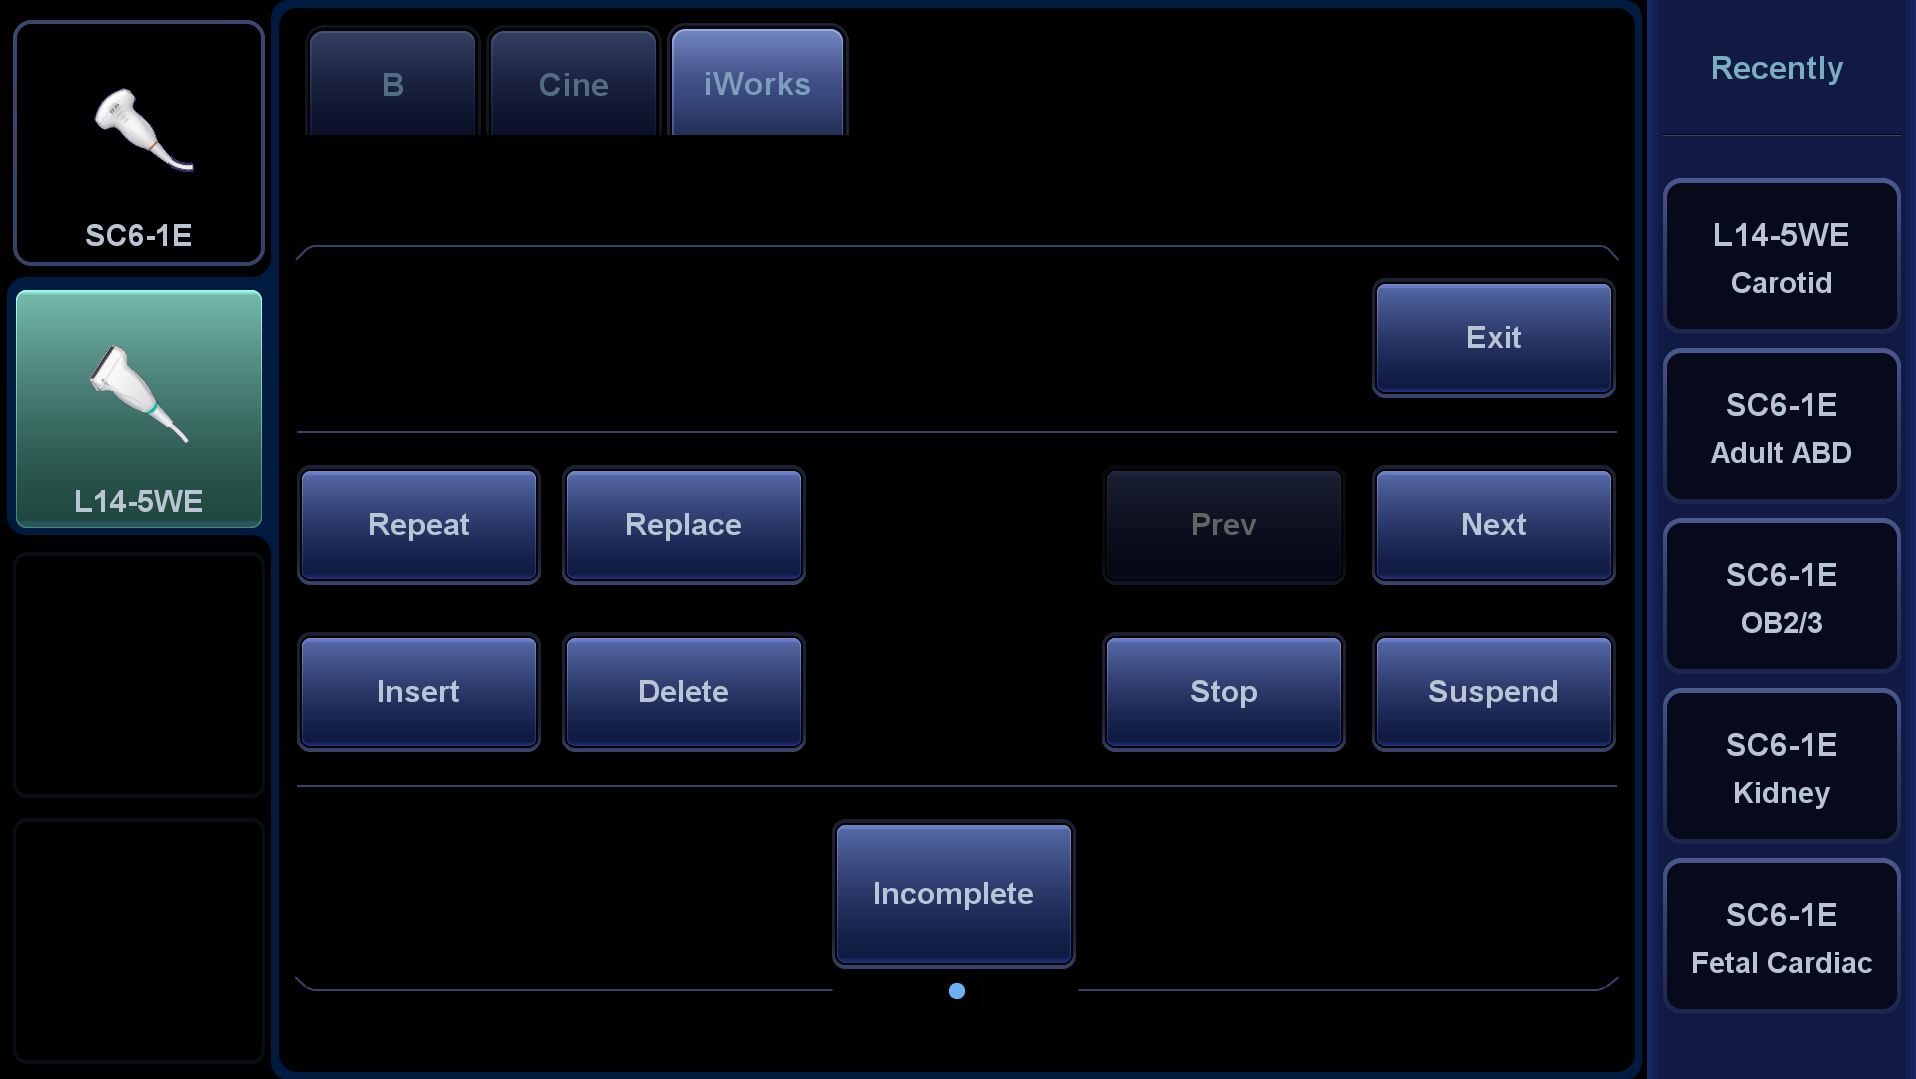

? Muayene protokolΟΦyle tutarl?l?k - iWorks

iWorks, daha fazla tutarl?l?k sa?lamak i?in dahili standart tarama protokollerini kullan?r ve muayene sΟΦresini %50'ye varan oranda azalt?r. Bu son derece esnek ve gΟΦ?lΟΦ ?zellik, kullan?c? tan?ml? ?zelliklerle daha da geli?tirilir.

- Muayene protokolΟΦyle tutarl?l?k --- iWorks

- iWorks, daha fazla tutarl?l?k sa?lamak i?in dahili standart tarama protokollerini kullan?r ve muayene sΟΦresini %50'ye varan oranda azalt?r. Bu son derece esnek ve gΟΦ?lΟΦ ?zellik, kullan?c? tan?ml? ?zelliklerle daha da geli?tirilir.